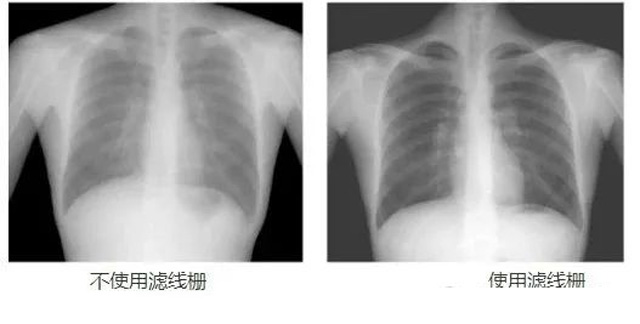

DR影像X射线在医学检查成像有着广泛的使用。但是它的散射线影响成像质量问题。滤线栅的发明使用很好的解决了这个问题,构造简单铅条粗,密度和栅比规格单一,能减散射线但吸收较多原发射线。伴随这医疗影像设备技术的发展,这个滤线栅的工艺制造技术有改进,铅条变薄,栅密度和栅比有更多的选择。特别是材料方面有新组合,填充物也依不同成像要求优化。特别是移动DR这类型的DR设备的出现,滤线栅也设计成立方便拆卸形的,方便使用。被照体情况决定是否使用,更好平衡成像质量与射线剂量。